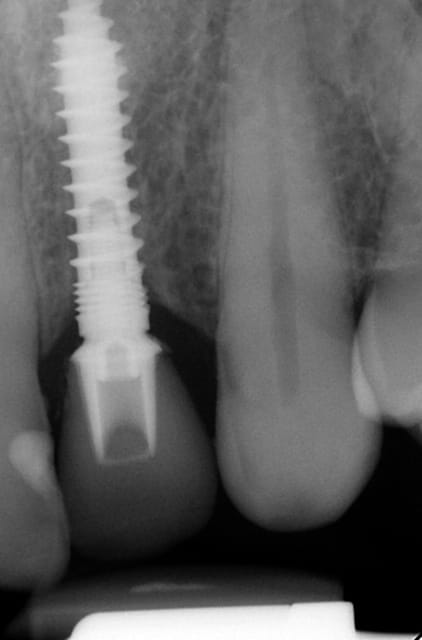

Merci pour tes questions. Si tu as une gencive "normale" (2-3 mm) ( avec le foret on peut savoir grâce aux mesures ) tu arrêtes à implanter si le truc en métal (je ne sais pas en francais en allemand Einbringhilfe) arrive à la gencive. Si la gencive fait plus de 3mm tu pousses un peu plus (le début de la fenêtre du Einbringhilfe est à un millimètre , la fin de la fenêtre = 3mm ) ...on vérifie avec une petite radio (pas OPG) .

Oui sans condenser juste en flapless ca serai moins évident. Pour moi-même en condensant j´ai besoin de 1 mm buccal minimum(plus il y a mieux c´est) mais dans ma pratique et celles mes confrères ca fonctionne et cela dure dans le temps depuis 16 ans.

En dessous il y a des photos, dans une on voit (troisième) qu il n y a pas de resorption de l´os après 14 ans, ce que l´on voit c´est l´os très fin condensé sur l´implant.